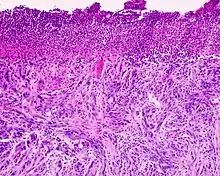

Desmoplastic melanoma is a rare cutaneous condition characterized by a deeply infiltrating type of melanoma[2]: 696 with an abundance of fibrous matrix.[3] It usually occurs in the head and neck region of older people with sun-damaged skin.[3] Diagnosis can be difficult as it has a similar appearance to sclerosing melanocytic nevi as well as some nonmelanocytic skin lesions such as scars, fibromas, or cysts.[3]